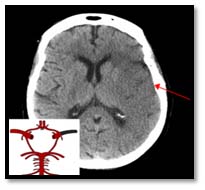

CT scans and MRI

Two common methods used for brain imaging are a computer tomography (CT) scan and magnetic resonance imaging (MRI) scan.

A CT scan is like an X-ray, but uses multiple images to build up a more detailed, three-dimensional (3D) picture of the brain.

Computed tomography (CT) scan